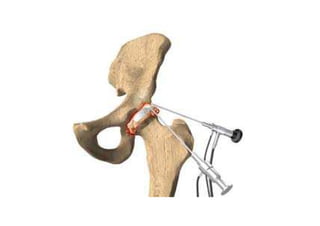

• Semiologia ortopédica armada (noções básicas de artroscopia)